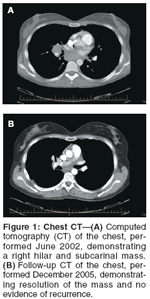

The patient did extremely well, up until 3 years after her original treatment. Unfortunately, an atypical isolated mass in the right hilum was found incidentally on a chest x-ray. A staging computed tomography (CT) scan of the chest and abdomen revealed a right hilar mass measuring 3.5 cm × 2.6 cm, with extensive subcarinal lymphadenopathy measuring 4 cm × 2.2 cm. No other abnormalities were identified. Following a nondiagnostic bronchoscopy, which revealed no abnormalities in the lower trachea or bronchi, biopsies of the subcarinal mass were performed via a mediastinoscopy. Histologic and immunohistochemical evaluation (along with comparison to her previous primary vaginal carcinoma) were undertaken. Pathology of the subcarinal mass was reported as metastatic squamous cell carcinoma consistent with spread from her vaginal primary.

The mass was deemed to be inoperable due to its location. In discussion with the patient, it was decided to approach the treatment of this isolated recurrence with radical curative-intent radiotherapy. The patient was treated with 6 MV photons using a three-dimensional conformal external-beam technique. A total dose of 7,500 cGy was delivered in 35 equal daily fractions, employing a gradual shrinking-field technique. She did experience the expected acute side effects of radiation esophagitis and pneumonitis. The radiation-induced pneumonitis was slow to resolve. In addition, she was found to have fibrotic pulmonary changes on follow-up chest x-ray and chest CT scan, secondary to her treatment.

On posttreatment CT scan of the chest, the mass had decreased dramatically in size, measuring 1.5 cm in greatest dimension. On follow-up positron-emission tomography (PET)/CT scans, no focal abnormalities have been identified. She is now 5 years post–radical radiotherapy for her right hilar and subcarinal recurrence of her primary squamous cell carcinoma of the vagina. She continues to do well, without evidence of disease recurrence, having only mild reactive respiratory symptoms, which are stable. Her son is now 7 years old.